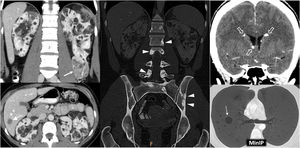

Hereditary papillary renal cell carcinoma (pRCC) in a 74-year-old male. Incidental finding. (A) (coronal) and (B) (axial; composite image). CT in nephrographic phase. Exophytic right renal cystic mass (arrows) with a solid nodule hypoattenuating with respect to the renal parenchyma (arrowheads). There is also an exophytic cortical mass, which is also hypoattenuating, near the contralateral kidney (*). A core needle biopsy of the solid component of the right solid nodule was performed, revealing a pRCC, and so percutaneous radiofrequency thermoablation was performed in the same procedure. (C) Coronal CT in the nephrographic phase one day after ablation. Loss of tension in the right cystic component (arrow) and small residual attenuating image (arrowhead), without enhancement compared to the non-contrast study (not shown). The contralateral lesion (*) showed absolute enhancement of 32 HU and was also suspected to be a pRCC. The urology department decided to perform a left nephrectomy, which confirmed this suspicion. In addition, numerous millimetric papillary adenomas were identified in the left kidney. (D) Axial CT (composite image) without contrast (due to renal failure) five years after nephrectomy. Image showing no recurrence in the right kidney (dashed arrow) and left nephrectomy (hollow arrow).

Hereditary leiomyomatosis and renal cell carcinoma. A 26-year-old female with constitutional symptoms, pain and a palpable mass in the left lumbar region. (A) MRI. Axial images with T1-weighted, T2-weighted, and parametric map of apparent diffusion coefficient. (B) Coronal non-contrast CT, nephrographic phase and excretory phase. Infiltrating mass measuring 135 mm in the left kidney (arrows). There are extensive cystic-necrotic and haemorrhagic areas (*), the latter with high T1 signal and water diffusion restriction, as well as papillary projections with subtle enhancement on CT, with an increase of between 23 and 31 HU in the nephrographic phase (arrowheads). It is accompanied by a tumour thrombus in the left renal vein, with similar characteristics. (C) Sagittal T2-weighted pelvic MRI performed three years earlier. Uterus with multiple hypointense fibroids (m). (D) Coronal CT image in the nephrographic phase one year after nephrectomy. Recurrence in the form of a heterogeneous mass in the surgical site (r) and liver metastases (dashed arrows). The nephrectomy specimen was initially diagnosed as papillary renal cell carcinoma type 2. Later, loss of FH staining was observed in a controlled immunohistochemical study, allowing for the diagnosis of this specific entity.

Tuberous Sclerosis Complex in a 45-year-old female. CT. Innumerable bilateral renal angiomyolipomas with gross fat. Its exophytic growth is noteworthy due to the risk of bleeding associated with its size and the abundance of aberrant vessels, one of which is in the lower pole of the left kidney (arrow). Hepatic angiomyolipomas are also visible (double arrow), along with sclerotic lesions in the axial skeleton (arrowheads), small subependymal calcified lesions (hollow arrows) and multiple thin-walled cystic lesions in both lungs (dashed arrow) in the context of pulmonary lymphangioleiomyomatosis.

Lynch syndrome in a 73-year-old male who previously underwent surgery for sigmoid colon adenocarcinoma. Haematuria. CT. Mass affecting renal pelvis (arrowhead) and infiltrating renal parenchyma (arrows) with scant enhancement. It corresponded to a urothelial carcinoma accompanied by enlarged retroperitoneal lymph nodes (*) and a synchronous bladder lesion (dashed arrow). See part of the mechanical colorectal anastomosis (hollow arrow).